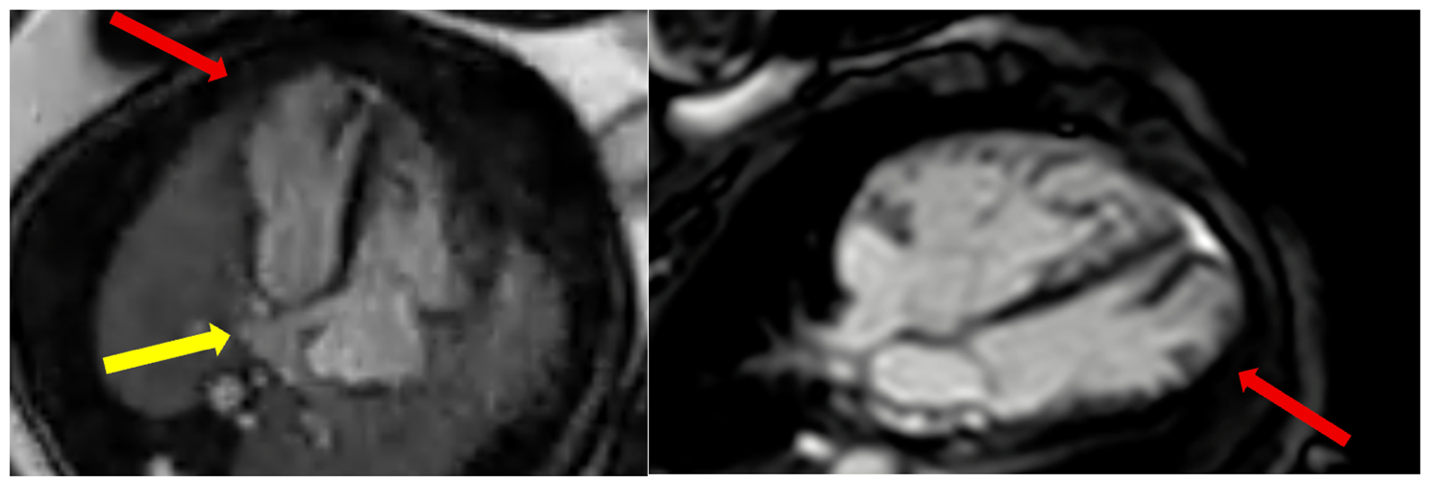

Figure 2: Fetal cardiac magnetic resonance (CMR) imaging in a 35 week fetus. Fetal Doppler-derived ECG gated balanced steady state free procession cine imaging in 4-chamber plane (left panel) shows a dilated coronary sinus with anomalous pulmonary venous drainage of at least three pulmonary veins draining into the coronary sinus (yellow arrow). Additionally, a large mid to apical left ventricular diverticulum was identified measuring 25 × 9 mm in diastole and 17 × 7 mm in systole (red arrow). Cine imaging on postnatal CMR (right panel) done in the first week of life with a comparative 4 chamber plane showing the left ventricular diverticulum (red arrow).